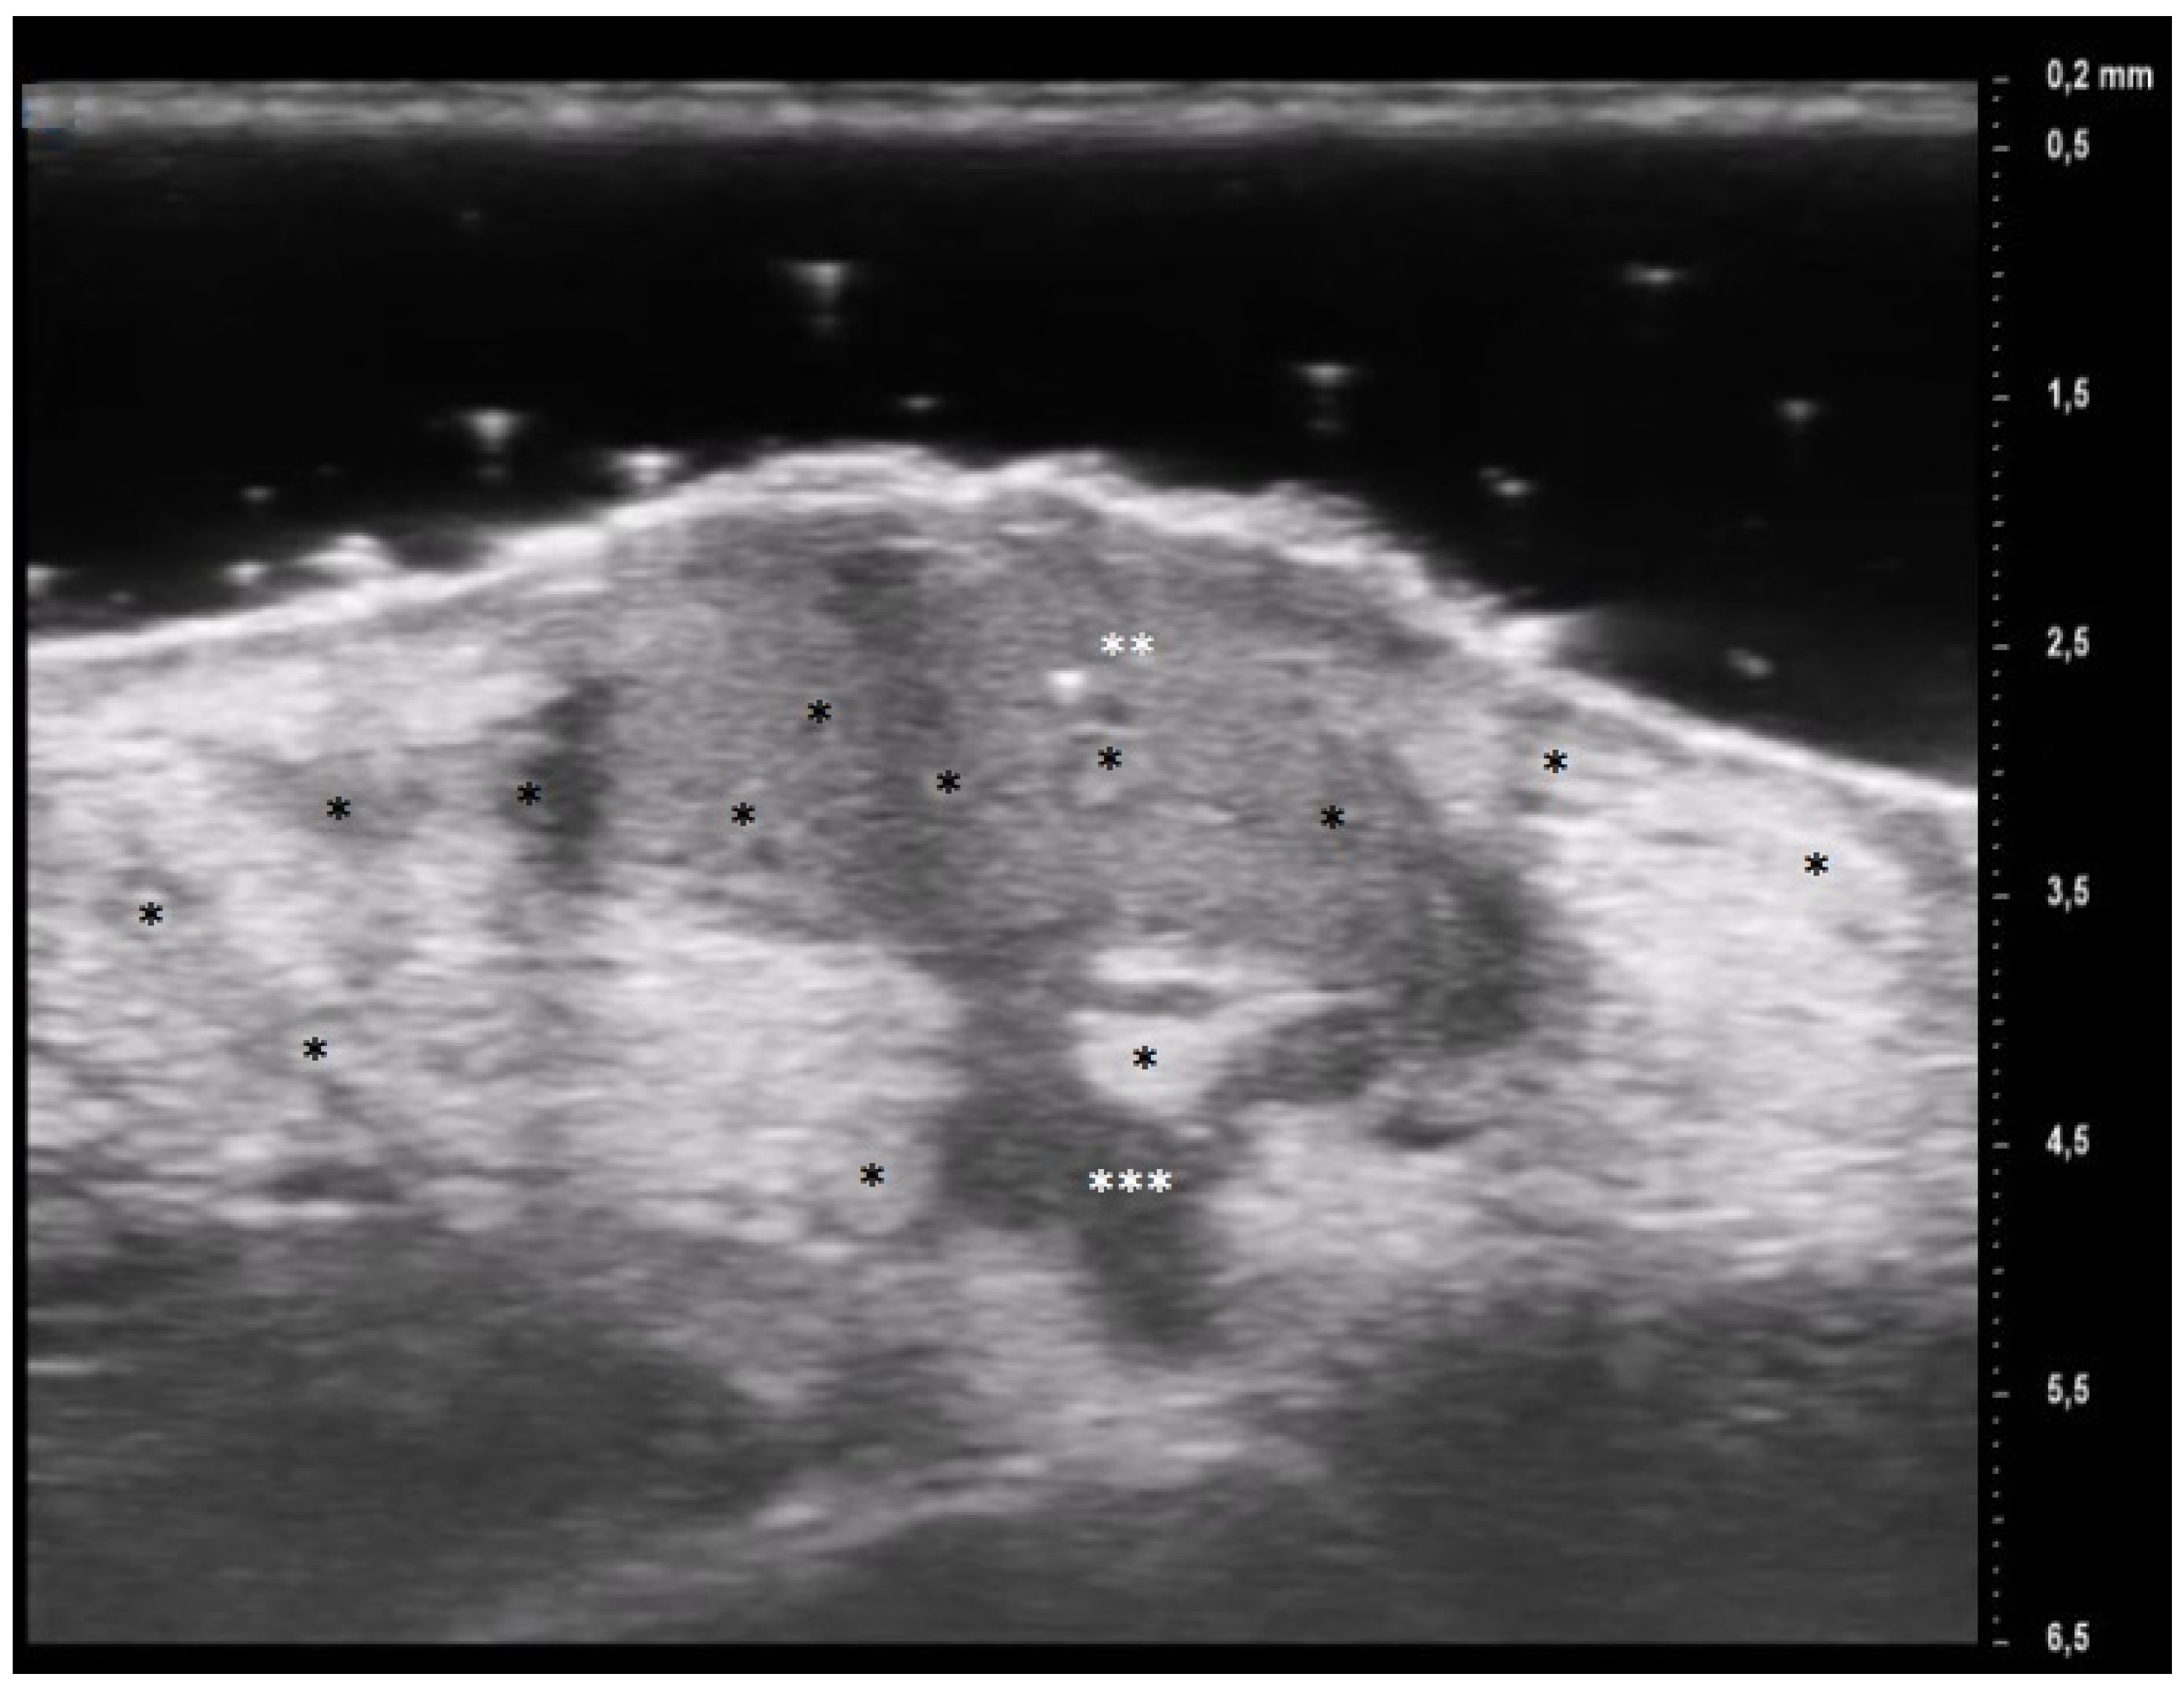

Figure 3.

PG pustular lesion: hyperecoic oval structures (*), hair tract (**), hypoechoic U-shaped and V-shaped vessels (***).